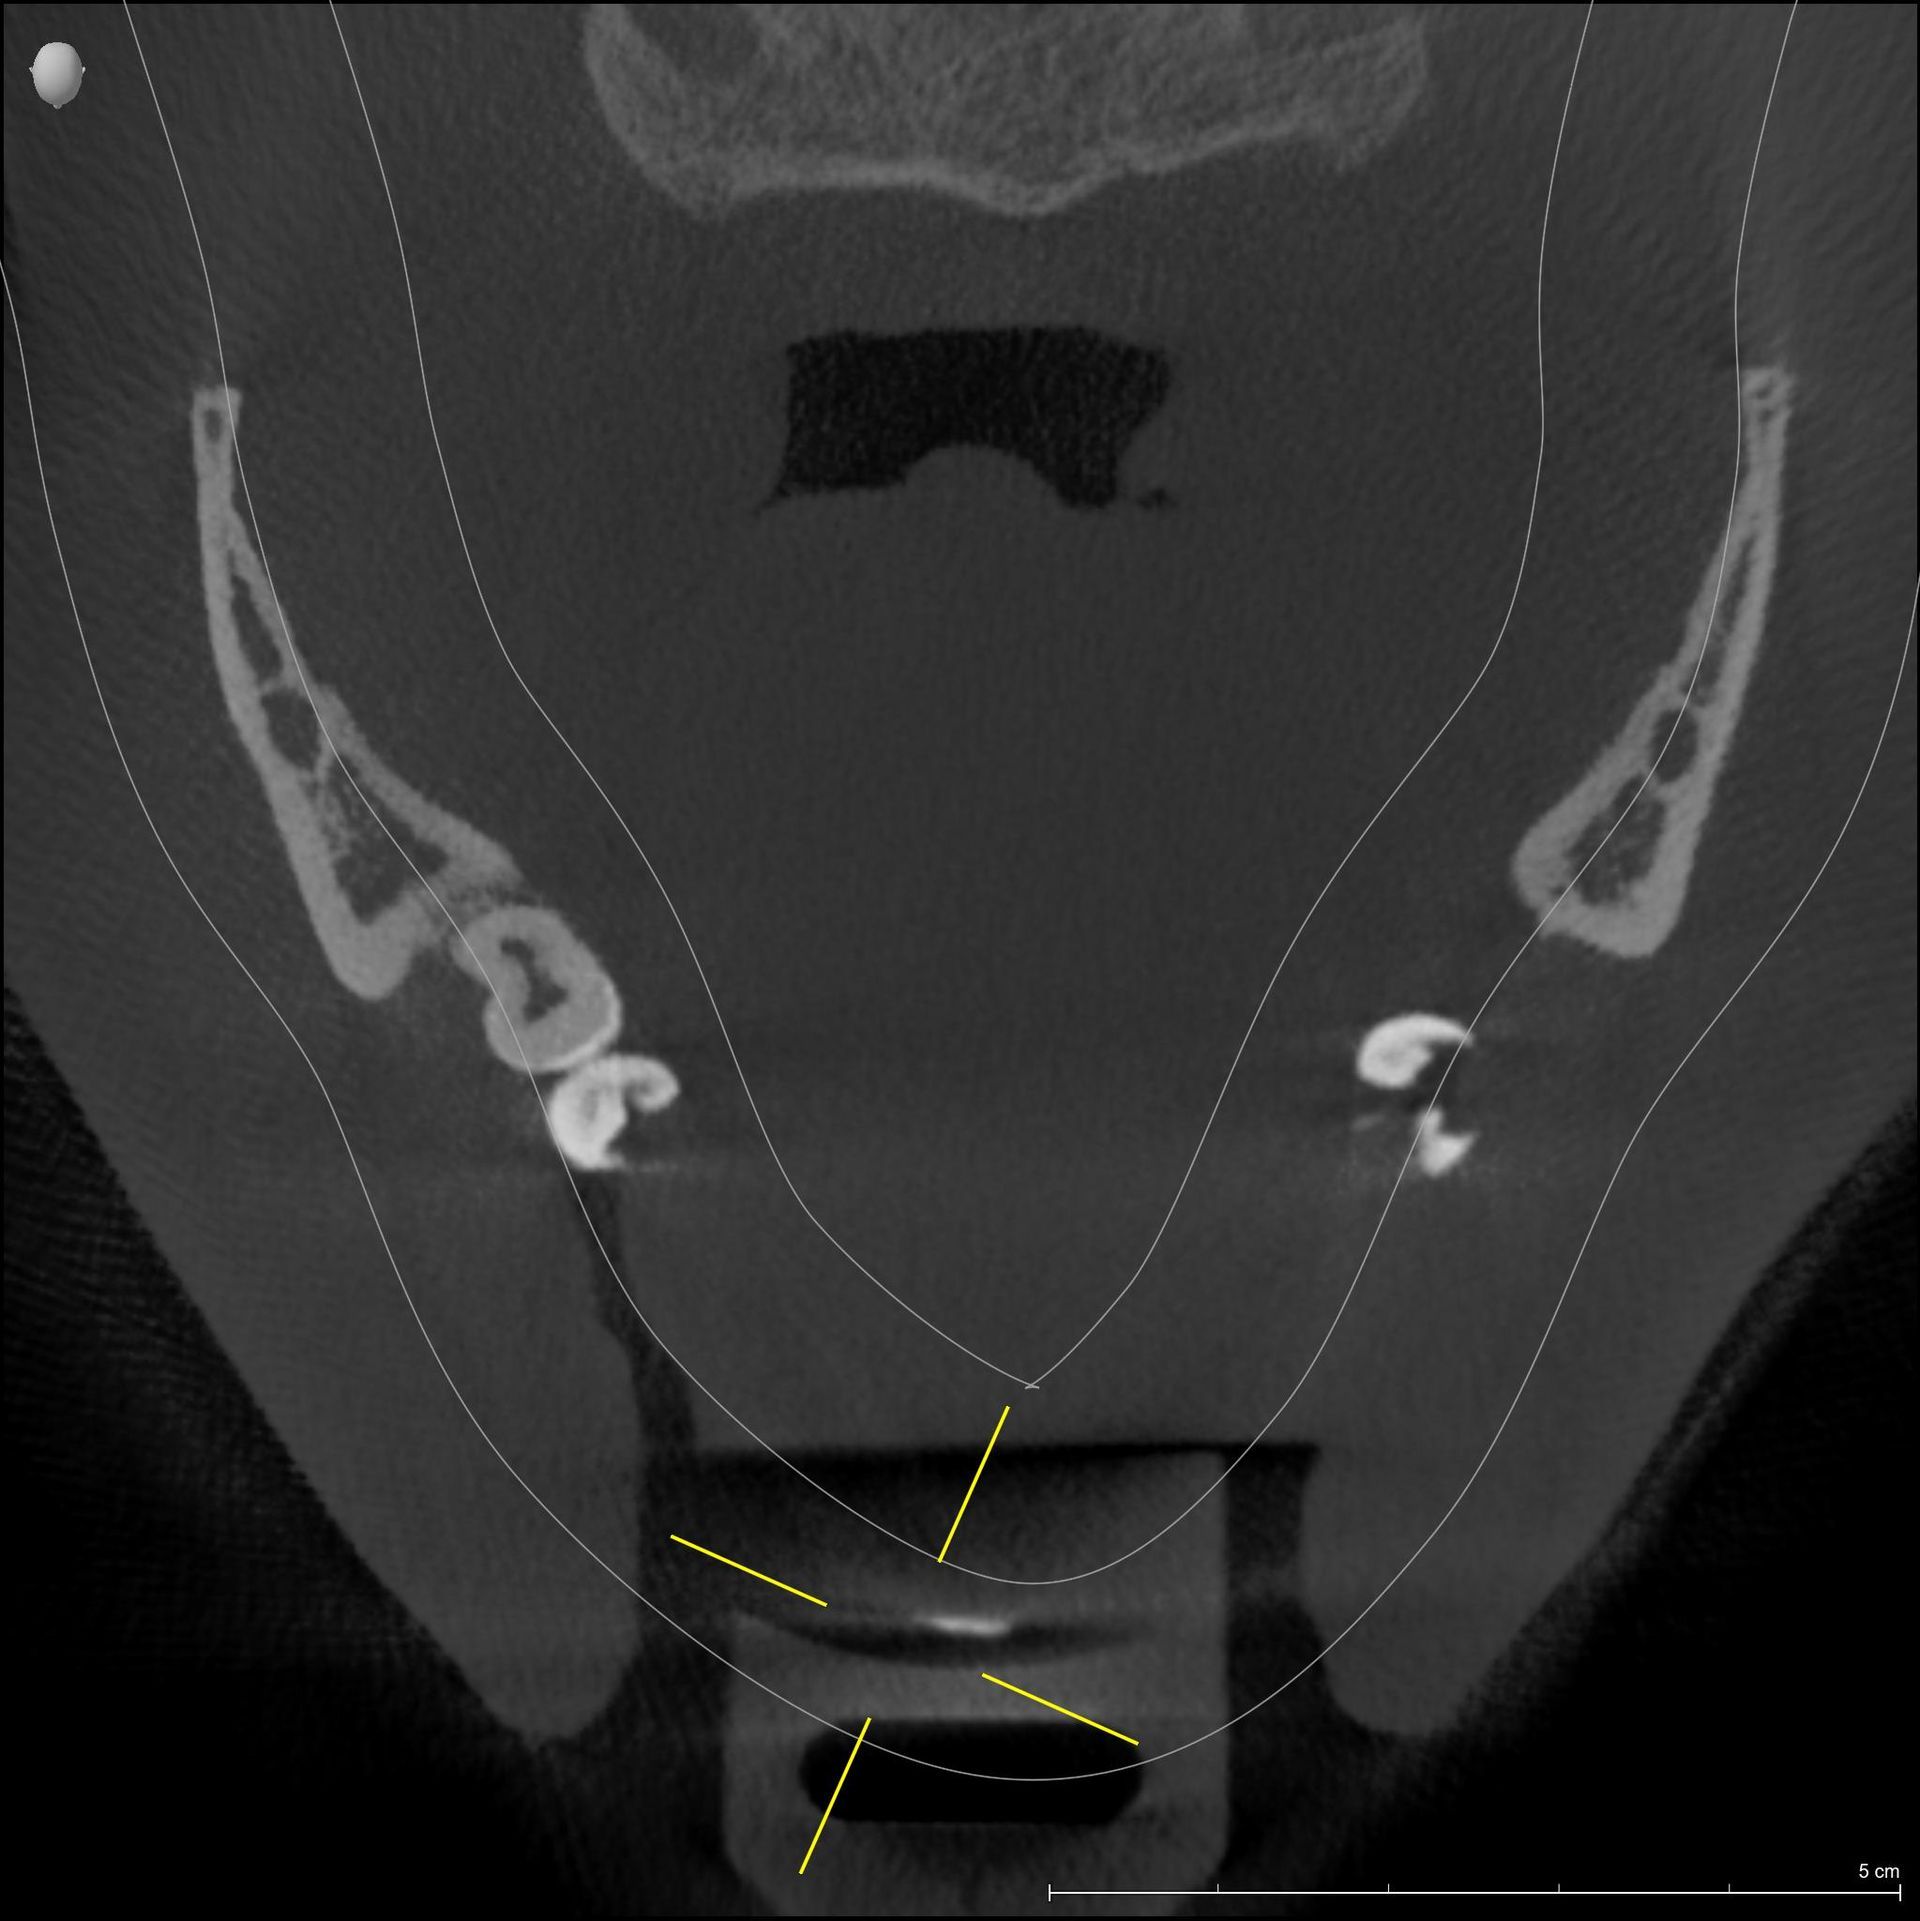

Esame diagnostico che permette di valutare, con precisione, la densità ossea mascellare e mandibolare, richiesto dai dentisti, in quanto indispensabile prima di un intervento di implantologia.

Trova indicazione anche in ortodonzia per lo studio dei denti inclusi, soprannumerari ed ectopici e in endodonzia.

La funzione 3D, permette la visualizzazione completa delle strutture dentarie, ossee, in tre dimensioni, con ottima risoluzione di contrasto per lo studio dei tessuti molli.